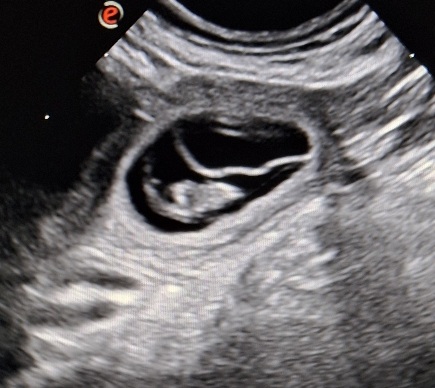

18.10.25 : Der Deckakt ist nicht ohne folgen geblieben.

Wir freuen und sehr, das wir Ende November Welpen erwarten

Tag 28 nach Deckung